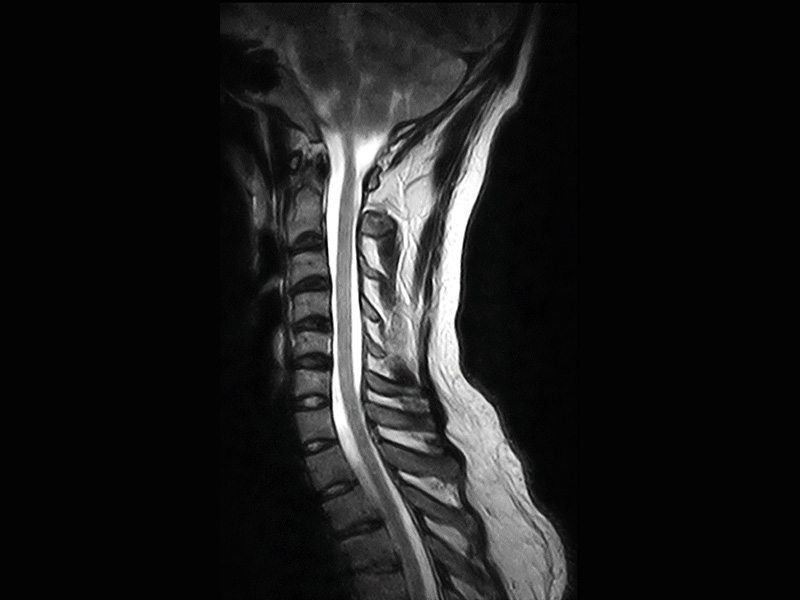

Klinické snímky